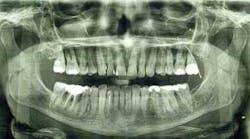

We saved three out of four molar areas (which have been functioning for 15 years now). The lost area is at teeth nos. 2 and 3. I remembered later that they had been damaged in an earlier dental matter. Tooth no. 2 was very loose, and no. 3 had a big crack in it.

After these teeth were removed, I tried getting a dental implant to replace no. 3, but for whatever reason, I was not comfortable, so we abandoned that treatment. I am now edentulous in that area, and I was advised to eat on the other side. Thus, our adventure began.